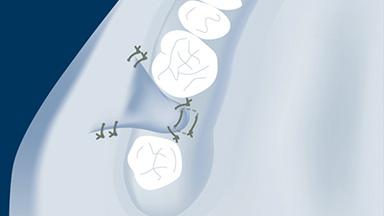

Fatores múltiplos influenciam o sucesso de cirurgias implantares. O que incluem planejamento cuidadoso do tratamento a ser realizado, conhecimento básico de técnicas cirúrgicas comuns a todos os procedimentos cirúrgicos e habilidade de executar estes procedimentos de maneira atraumática. Um destes procedimentos é o fechamento de qualquer retalho gengival que foi rebatido durante a cirurgia. O objetivo do fechamento de retalhos tecidual é reposicionar os tecidos moles gengivais em uma posição anatômica adequada. O fechamento satisfatório do retalho cirúrgico tecidual promove a cicatrização e reduzir complicações como abertura, deiscência e infecção da ferida. Esses fatores desempenham um papel importante na obtenção de resultados cirúrgicos bem-sucedidos e estéticos. Este módulo se concentrará no fechamento do retalho gengival para cirurgia oral relacionada aos procedimentos de implante.

- descrever os princípios cirúrgicos gerais do fechamento de retalhos gengivais, incluindo o processo de cicatrização tecidual

- descrever os princípios cirúrgicos do fechamento de retalhos gengivais após cirurgias implantares

- explicar as complicações associadas com o fechamento de retalhos gengivais